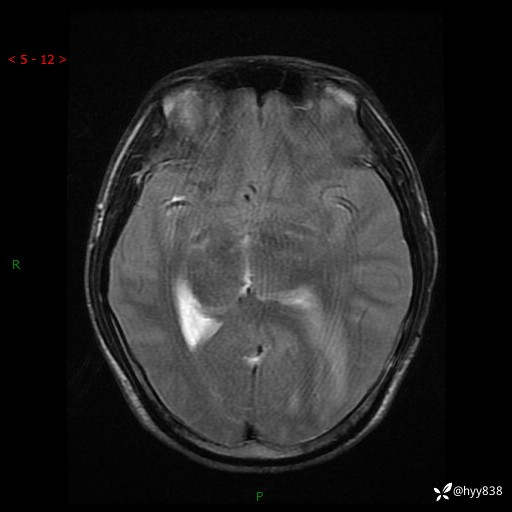

病例年轻小伙,头痛伴呕吐半年,渐进性加重1月。疑难病例,第一次见--结果公布~

性别:男

年龄:21岁

简要病史:头痛伴呕吐半年,渐进性加重1月

颅脑MRI平扫+增强